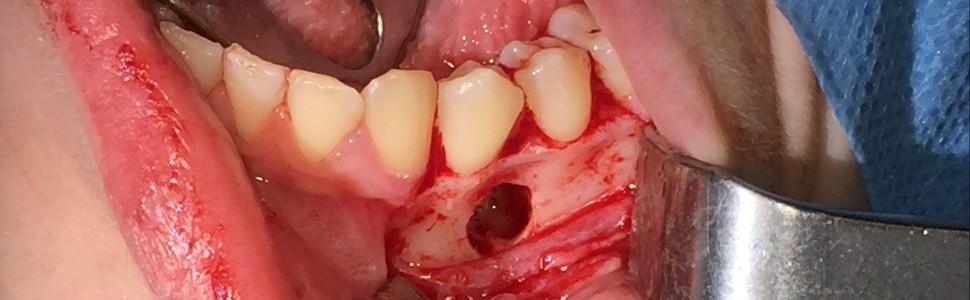

Zaburzenia związane ze zwiększoną liczbą uzębienia w jamie ustnej stanowią częsty problem w praktyce lekarza dentysty. Mimo to przypadki licznych zębów nadliczbowych należą do rzadkości. Jedną z przyczyn tej anomalii jest zwiększona aktywność listewki zębowej podczas rozwoju układu stomatognatycznego. Obecnie nie opracowano jednoznacznych metod leczenia. Każdy przypadek wymaga współpracy wielospecjalistycznego zespołu terapeutycznego. W artykule przedstawiono przypadek małoletniej pacjentki, u której rozpoznano mnogie zęby nadliczbowe żuchwy zlokalizowane w okolicy zębów przedtrzonowych.

Disorders associated with an increased number of teeth in the oral cavity are a common problem in dental practice. Still, cases of numerous supernumerary teeth are rare. One of the causes of this anomaly is the hyperactivity of the dental lamina during the development of the stomatognathic system. There are currently no clear recommendations indicating the most appropriate course of action. Each case requires consultation of a multi-specialist therapeutic team. The paper presents the case of a young patient who was diagnosed with multiple supernumerary teeth in mandible located near premolars.